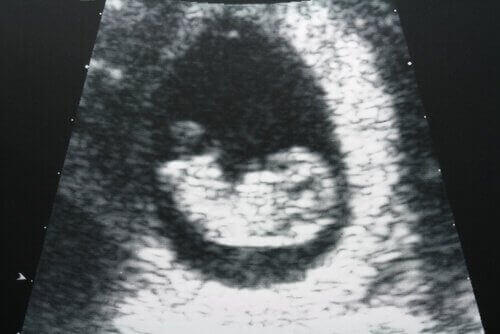

Ultraäänitutkimus on erittäin tarkka diagnostiikkakeino, jonka avulla voidaan selvittää, ilmeneekö kohdussa tai munasarjoissa ongelmia.